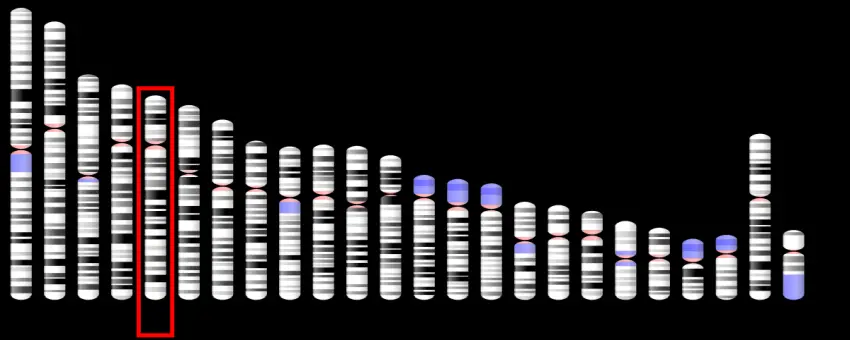

Il nuovo microscopio Firefly è ottimizzato per eseguire studi optogenetici esaminando molti neuroni contemporaneamente. Ogni punto luminoso qui rappresenta un neurone di un topo geneticamente modificato.Un microscopio appena sviluppato sta fornendo agli scienziati uno strumento notevolmente migliorato per studiare come i disturbi neurologici come l'epilessia e l'Alzheimer influenzano la comunicazione neuronale.

Il nuovo microscopio Firefly è ottimizzato per eseguire studi optogenetici esaminando molti neuroni contemporaneamente. Ogni punto luminoso qui rappresenta un neurone di un topo geneticamente modificato.Un microscopio appena sviluppato sta fornendo agli scienziati uno strumento notevolmente migliorato per studiare come i disturbi neurologici come l'epilessia e l'Alzheimer influenzano la comunicazione neuronale.